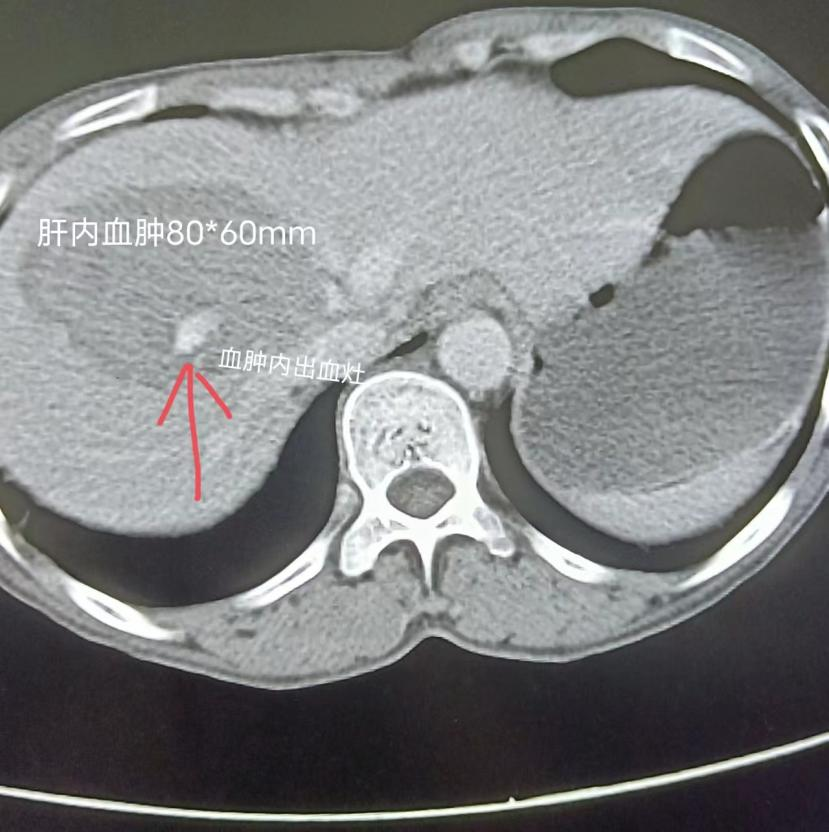

“五一”国际劳动节这天的下午六点钟左右,接普外科急会诊电话——外伤性肝破裂出血!优米nba直播介入团队来不及享用假日家庭聚会紧急赶到医院,详细了解病人的基本情况。结合增强CT及相关辅助检查结果后,姚金顺主任初步判断系肝动脉系统血管损伤,为慎重起见,并将病人资料发往上级医院多位专家会诊,明确介入治疗方案后,与患者及家属沟通取得同意紧急行肝动脉造影+经导管肝动脉栓塞术!荧光灯下,一场介入导管室医护与时间赛跑的战斗正式打响……

消毒、铺巾、穿刺、插管,有条不紊地进行着,行腹腔干造影,发现血管走形变异,尝试使用多种型号导管超选进入肝动脉困难。姚金顺主任及江张兵医师尝试用A型号导管挂住入口导丝深入后更换B型号导管终于成功进入肝固有动脉内,行DSA造影显示肝右叶分支动脉造影剂外溢,血液从破口向外流出,假性动脉瘤形成。为尽量多的保留患者的肝组织、保护其肝功能,采用同轴导管技术将微导管置入出血的肝动脉近端,经“三明治”栓塞法栓塞后成功将出血肝动脉栓塞,造影复查未见明显造影剂外溢,止血成功。手术顺利,患者无明显不适。